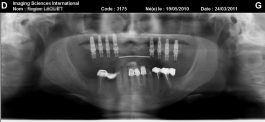

L’intervention chirurgicale consiste en une reconstruction osseuse du maxillaire ou de la mandibule avant la mise en place des implants dentaires par votre chirurgien.